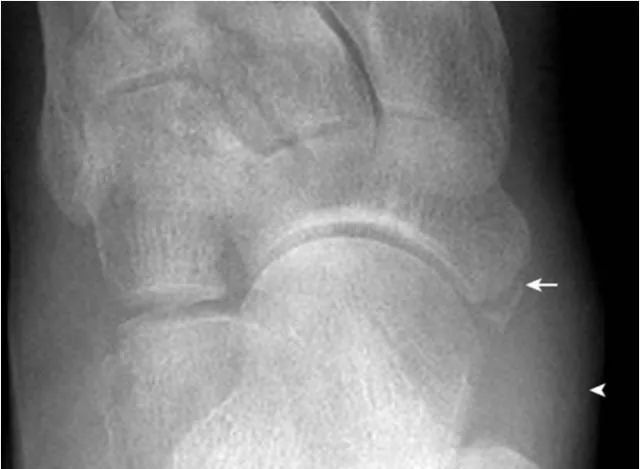

5.楔舟内侧骨:

内侧楔骨与足舟骨之间的内侧,可见小的骨性结节(箭),为正常变异。需与撕脱骨折鉴别。另可见舟骨副骨(箭头)。